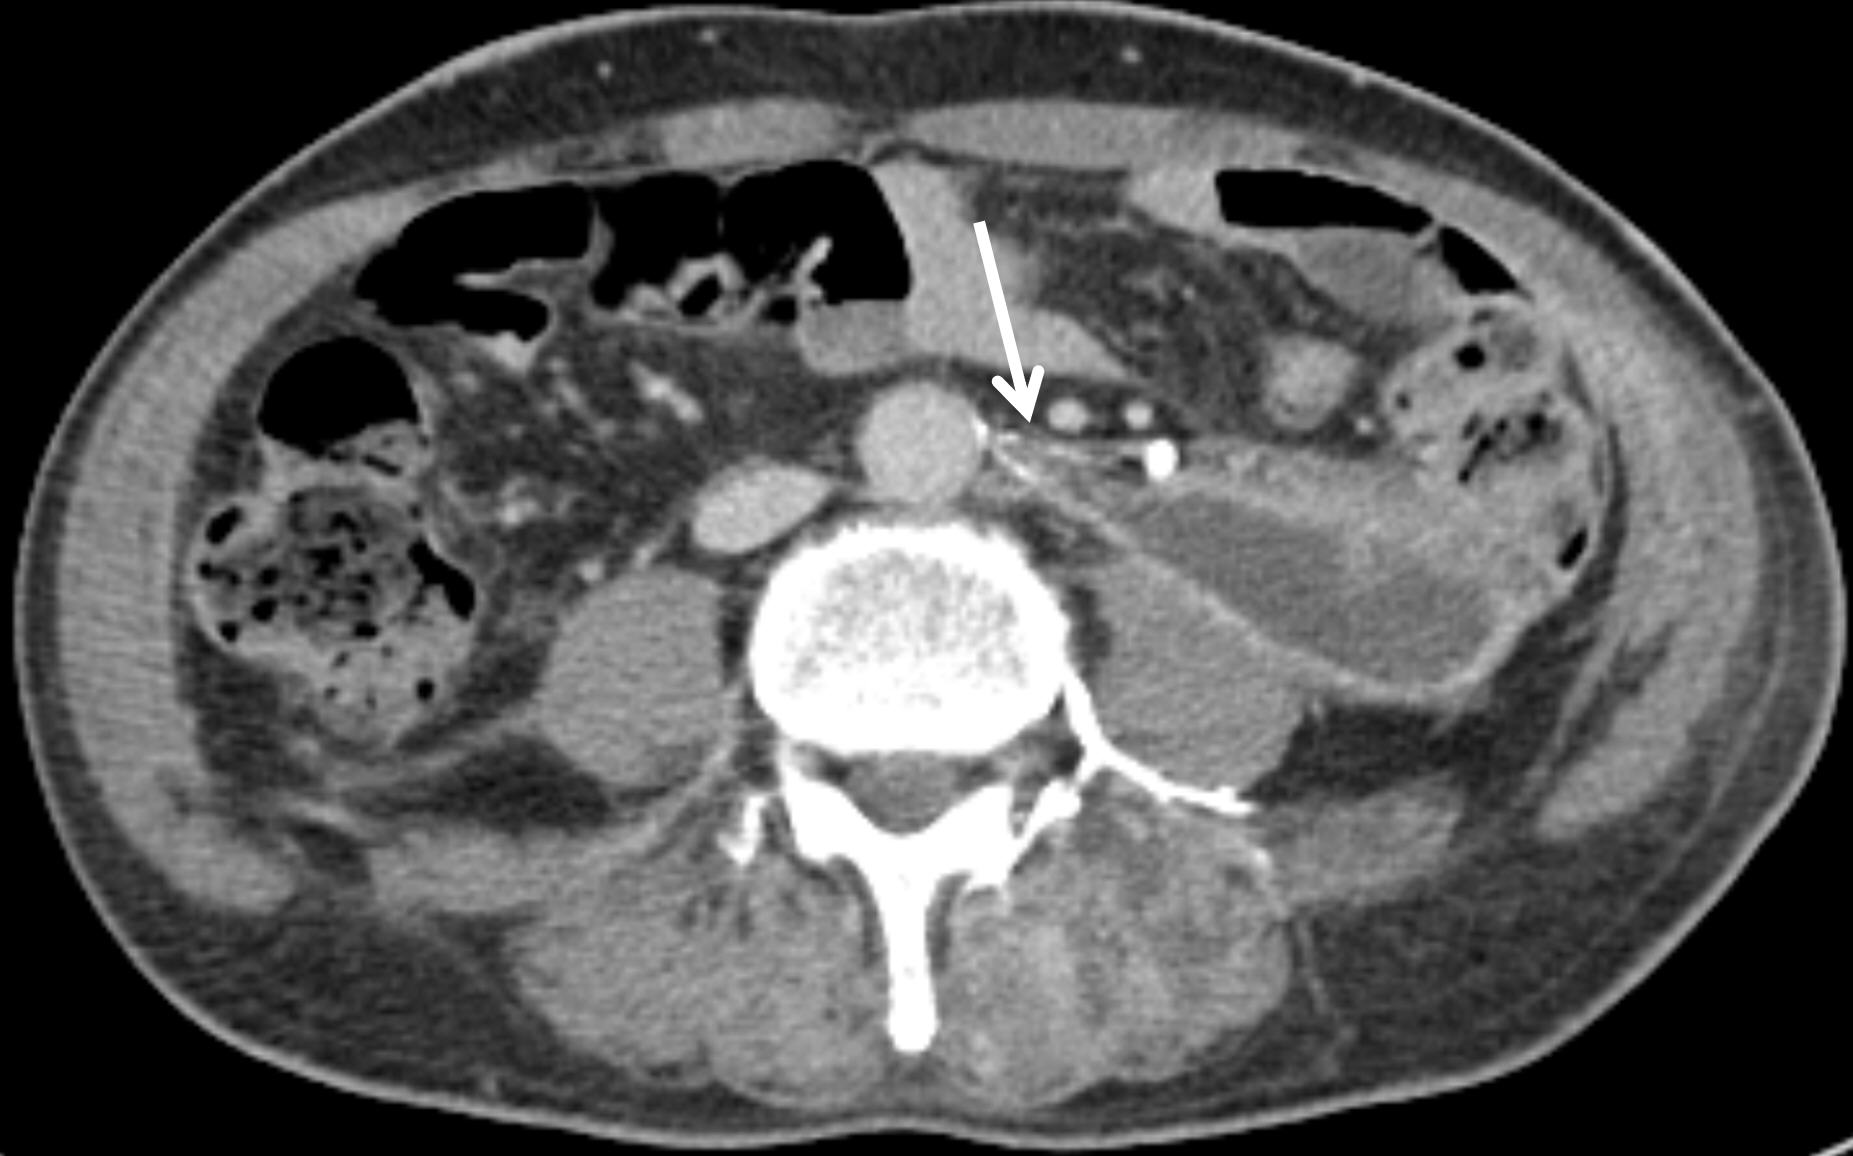

Seven hours after the empirical embolization procedure, the patient remained hypotensive despite intravenous hydration and blood transfusion. Repeat contrast-enhanced CT demonstrated an increase in the size of the left retroperitoneal hematoma with persistent active bleeding. Selective angiography of the infrarenal abdominal aorta branches—including the left renal and renal capsular arteries, left testicular artery, and inferior mesenteric artery—showed no evidence of hemorrhage. As bleeding was presumed to originate from a fine arterial branch not visualized on selective angiography, a 5-Fr diagnostic catheter (pigtail catheter; Jungsung Medical, Seoul, Korea) was positioned in the suprarenal abdominal aorta, and cone-beam CT was performed using a 7 mL/sec injection of a total of 70 mL of contrast (Visipaque 270mg I/ml, GE Healthcare, Shanghai, China).

Axial cone-beam CT images revealed a thin artery arising at the 12 o’clock position from the infrarenal aorta, which coursed leftward toward the left ureter, made an L-shaped bend, and descended, with active bleeding observed (

Fig. 2). Based on these findings, selective catheterization of this artery was achieved using the 5-Fr diagnostic catheter (RH; Jungsung Medical, Seoul, Korea) and a 1.5-Fr microcatheter (Veloute Ultra, Asahi Intecc, Nagoya, Japan). Embolization was then performed using a 1:4 mixture of NBCA and ethiodized oil.

Fig. 2.Axial and coronal cone-beam CT images as well as angiographic image, obtained during the procedure, demonstrate a bleeding left ureteric artery (arrows) originating from the abdominal aorta in the 12 o’clock direction and coursing posterolaterally to the left before sharply angling into an L-shaped configuration.